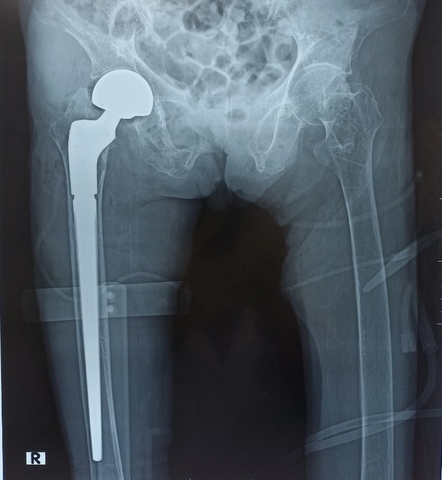

Phẫu thuật Thay khớp háng bán phần chuôi dài

Phẫu thuật thay khớp háng bán phần hay tạo hình đầu gần xương đùi một phần là một phẫu thuật chỉnh hình dùng để điều trị cho các trường hợp gãy khớp háng (cổ xương đùi, gãy liên mấu chuyển xương đùi). Trong đó, chỏm xương đùi sẽ được cắt bỏ và thay thế bằng các bộ phận có chất liệu như: kim loại, titanium, nhôm, cobalt hoặc nhựa rất cứng…

Phương pháp phẫu thuật này thường được chỉ định cho những trường hợp gãy cổ xương đùi di lệch nhiều trên bệnh nhân cao tuổi hoặc người không đảm bảo sức khỏe để thực hiện các ca mổ dài và phức tạp.

- Phẫu thuật thay khớp háng bán phần chuôi dài không xi măng